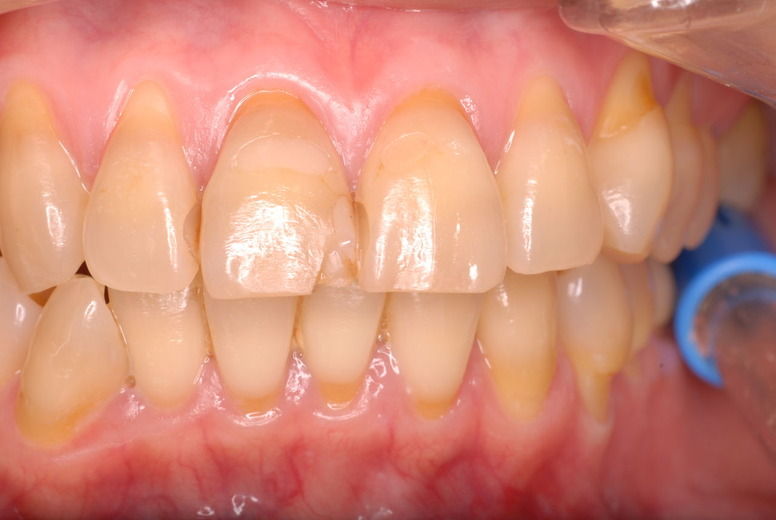

歯周病の疑いで東京のかなり遠方の方が来院されました。

驚くべきことですが、定期検診は受けていたそうです。しかしながら歯周病の指摘は受けたことがないそうです。

何故か?定期検診が虫歯のチェックのみになり、又肝心の歯周病の検査や歯周病の部分の予防や治療のためのブラシの使い方などを学んだ事がないのです。

本当に患者さんのことを考えると憂鬱になります。歯周病が悪化すると殆ど回復は無理だからです。